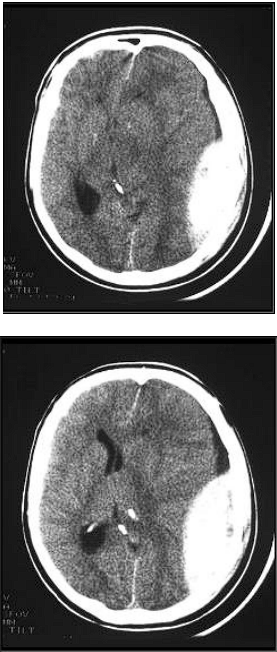

Paciente de 26 anos de idade, sexo masculino, vítima de

acidente motociclístico contra anteparo fixo. Segundo

informações da equipe de atendimento pré-hospitalar, o

paciente foi encontrado sem capacete e andando na cena

do acidente. Posicionado em prancha rígida com colar

cervical, evolui durante o transporte com rebaixamento do

nível de consciência. Na entrada no departamento de

emergência apresentava via aéreas aparentemente pérvias,

frequência respiratória de 18 incursões por minuto,

expansibilidade torácica simétrica e bilateral, frequência

cardíaca de 110 batimentos por minuto, pressão arterial de

100x60mmHg, abertura ocular a estímulos dolorosos,

ausência de resposta verbal, resposta motora flexora

inespecífica (sem localização) a estímulos dolorosos. Notou-se que o paciente movimentava apenas o dimídio esquerdo.

Anisocórico (pupila esquerda midriática). Tomografia sem

contraste.